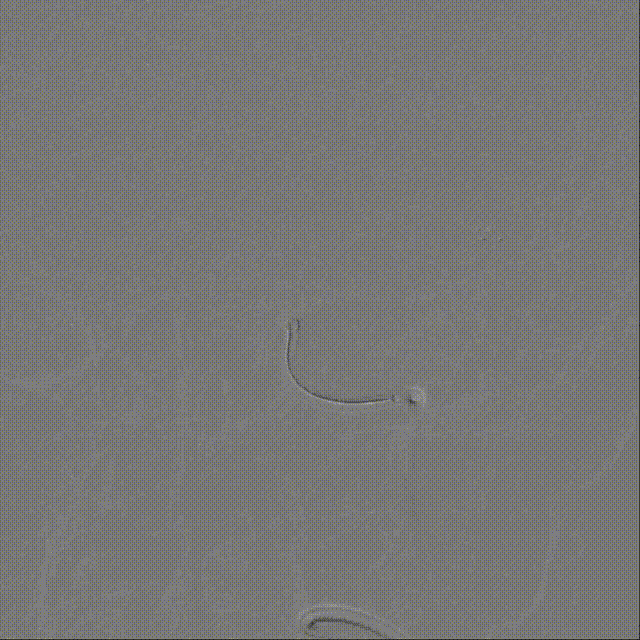

取出栓子: